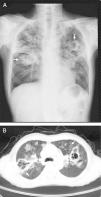

A 59-year-old man with no medical history presented with productive cough and hemoptysis for two months. Low-grade fever, fatigue and body weight loss were noted. Physical examination disclosed crackles in both lungs and cachectic appearance. Blood examination revealed hypoalbuminemia and generalized inflammation with a high C-reactive protein level. Chest radiography and computed tomography showed multiple cavities of various sizes and segmental consolidations in both lungs with upper lobes predominance (Fig. 1A and B). He was admitted under the impression of pulmonary tuberculosis initially. Sputum acid-fast stain and tuberculosis culture did not yield tuberculosis bacilli. Sputum culture yielded Aspergillus fumigatus later and ultrasound-guided fine-needle aspiration of a pulmonary nodule showed hyphae consistent with Aspergillus spp. Chronic pulmonary cavitary aspergillosis was diagnosed. Serial survey did not show evidence of immunodeficiency. After a 6-month course of voriconazole therapy, both symptoms and images remarkably improved (Fig. 2) and body weight increased. Longer duration of antifungal therapy is indicated.

Aspergillosis is an illness caused by aspergillus organisms with various manifestations. Chronic cavitary pulmonary aspergillosis is a multicavitary disease in immunocompetent patients and progresses over time. Previous mycobacterium infections, allergic bronchopulmonary aspergillosis and chronic obstructive pulmonary disease are the most common predisposing conditions.1 Most patients are often suspected of having tuberculosis initially. The common symptoms include cough, shortness of breath, hemoptysis and body weight loss. Radiographic examination usually disclosed multiple cavities of various sizes and ill-defined regions of consolidation, mainly in upper lungs. Diagnosis can be made by classical clinical and radiographic presentations combined with a positive aspergillus serology and/or culture of Aspergillus spp. from the lungs.2 Antifungal agents are the mainstays of therapy. Lifelong therapy is often required.3,4